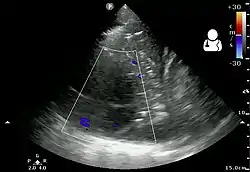

The initial investigations for suspected empyema remains chest X-ray, although it cannot differentiate an empyema from uninfected parapneumonic effusion.[5] Ultrasound must be used to confirm the presence of a pleural fluid collection and can be used to estimate the size of the effusion, differentiate between free and loculated pleural fluid and guide thoracocentesis if necessary. Chest CT and MRI do not provide additional information in most cases and should therefore not be performed routinely.[6] On a CT scan, empyema fluid most often has a radiodensity of about 0-20 Hounsfield units (HU),[7] but gets over 30 HU when becoming more thickened with time.[8]